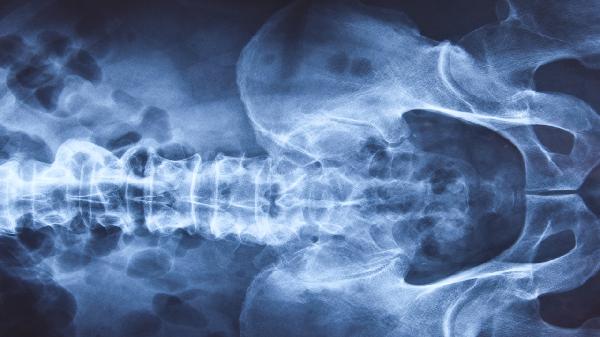

CT检查前的注意事项有哪些

CT检查前需注意空腹、去除金属物品、告知过敏史、穿着适宜衣物、避免剧烈运动等事项。

空腹要求通常适用于腹部或增强CT检查,检查前4-6小时需禁食固体食物,2小时前禁水,避免胃肠内容物干扰成像或造影剂引发呕吐。增强CT需提前确认肾功能,因造影剂可能加重肾脏负担。检查前应摘除项链、耳环、皮带扣等金属物品,防止产生伪影影响诊断准确性。有碘过敏史、哮喘或甲状腺疾病者需主动告知医生,评估是否适合使用含碘造影剂。建议穿着无金属配件的棉质衣物,女性避免穿带钢圈内衣。检查前24小时避免剧烈运动,防止肌肉劳损或乳酸堆积干扰影像判断。孕妇或备孕人群应提前说明情况,权衡检查必要性。